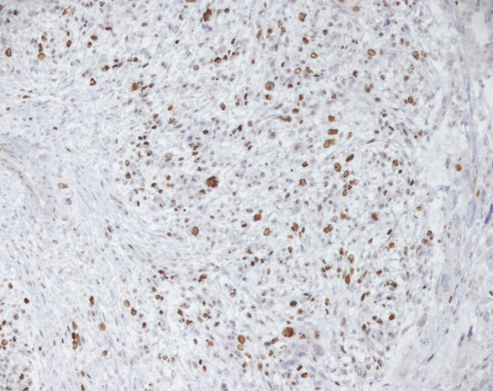

A final histopathology diagnosis of high-grade leiomyosarcoma, (see figure 1), (G3, FNCLCC 1986) pT2b pN0 pM0, AJCC (2002) Stage III, was made based upon immunoreactivity to smooth muscle actin, score 2 (see figure 2). The tumour specimen exhibited negative staining for c-kit and EGFR. Her proliferation index was 90%, which was evaluated thru MIB-1 (Ki-67) (see figure 3). Necrosis was inferior to 50% (score 2) and mitotic index higher than 20 mitoses per field/10 HPF (score 3). The tumour presented, macroscopically, as a bulky, brain-like, white-greyish mass. The tumour was noted to contain diverse necrotic and haemorrhagic areas, and invaded the vesical wall. The size of the mass was 14 cm × 11 cm × 6.5 cm. Histopathology examination of the specimen confirmed that the uterus and adnexa were free from neoplastic invasion. The surgical margins resulted negative at the final examination. LVI was not reported.

Figure 2.

Leiomyosarcoma of the bladder (Smooth muscle actin). Reproduced from: [2] under Creative Commons Attribution License